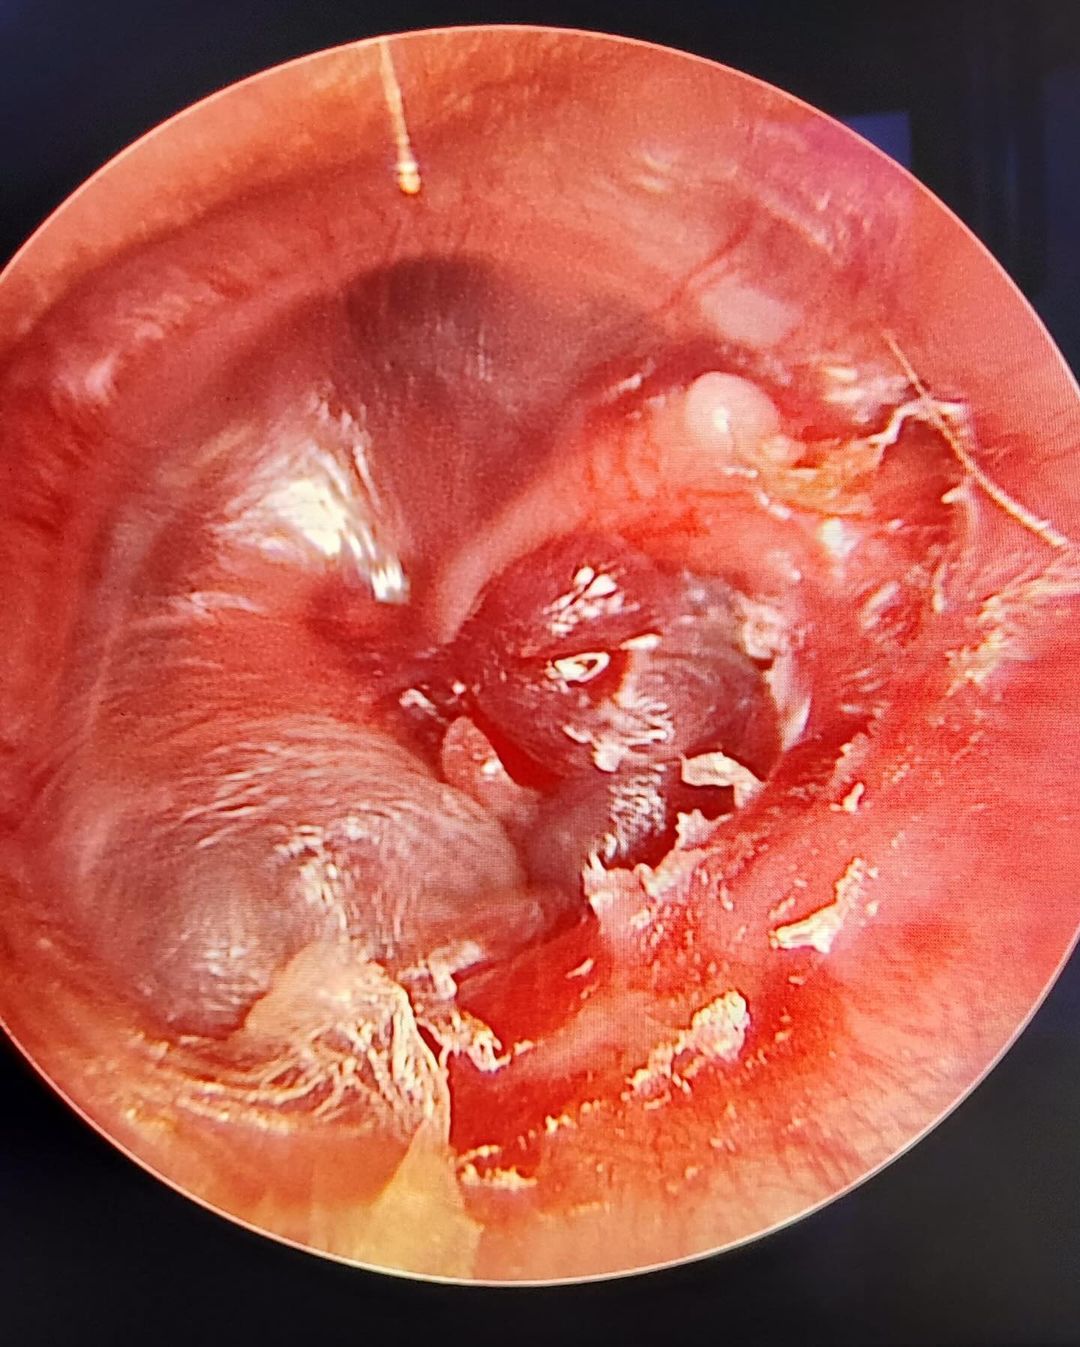

Tıbbi Resim Galeri